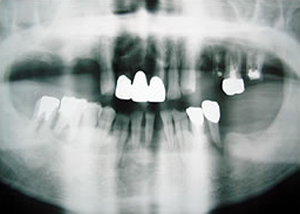

症例4 57歳女性

2009 6/21 更新

治療前

(下11本、上1本抜歯済み)